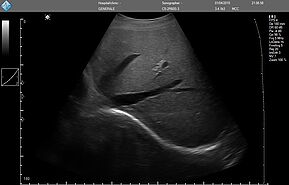

E-FAST имеет высокую чувствительность и специфичность (особенно в условиях гипотонии), может быть выполнен быстро, неинвазивно, без лучевой нагрузки, и может проводиться повторно. Благодаря таким преимуществам ультразвук по существу заменил диагностический перитонеальный лаваж (ДПЛ) при обследовании пациентов с травмой.

Положительный E-FAST у гемодинамически нестабильного пациента может указывать на необходимость проведения немедленного вмешательства (например, зондовой торакостомии, перикардиального окна, диагностической лапаротомии).

У гемодинамически стабильного пациента расширенная фокусированная оценка с сонографией при травме (E-FAST) может направлять дальнейшие диагностические исследования.

Хотя неотложный ультразвуковой протокол E-FAST был разработан для ускорения оказания помощи пострадавшим пациентам, применение его компонентов оказалось эффективным в случае использования портативного аппарата УЗИ (point-of-care ultrasound - POCUS) для обследования неповрежденных пациентов с гипотензией с целью выявления свободной жидкости, образовавшейся по другим причинам (например, при разрыве при внематочной беременности, аневризме брюшной аорты).